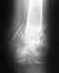

8 августа дочь, 19 лет, сбила машина, в результате открытый осколочный перелом обеих костей голени, в настоящее время лежит на вытяжке, рана еще не зажила.Какое лечение можно порекомендовать на данный момент и куда можно обратиться за помощью. Спасибо

Можно порекомендовать по крайней мере до заживления раны фиксацию аппаратом. После заживления мягких тканей решать о целесообразности смены наружной фиксации на блокируемый стержень. Для более определенных ответов не хватает информации о том, что именно с раной сейчас. Где сейчас больная? Это насчет "куда можно обратиться".